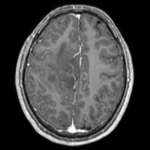

this is the fixed reference image. All images are aligned into this space lleft this is the T2 reference image, serves as target to the DTI baseline, but is itself aligned to the SPGR lleft DTI Baseline this is the DTI tensor image, in the same orientation as the DTI Baseline

T1 SPGR

fixed image 1

T2